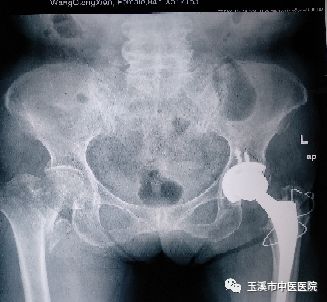

術(shù)前影像資料

近日,玉溪市中醫(yī)醫(yī)院收治了一位85歲的患者王奶奶,在4年前因跌倒致左股骨頸骨折到我院住院治療,行左側(cè)人工全髖關(guān)節(jié)置換術(shù)。2018年9月7日,王奶奶再次因為跌倒致右股骨粗隆間骨折至我院關(guān)節(jié)與運動醫(yī)學(xué)科(骨傷二科)住院治療,予患者行右側(cè)人工半髖關(guān)節(jié)置換,現(xiàn)患者已經(jīng)開始下地活動。對于老人家來說,經(jīng)歷了兩次“人生最后一次骨折”是“不幸”,但還能再次站立起來行走是“萬幸”。